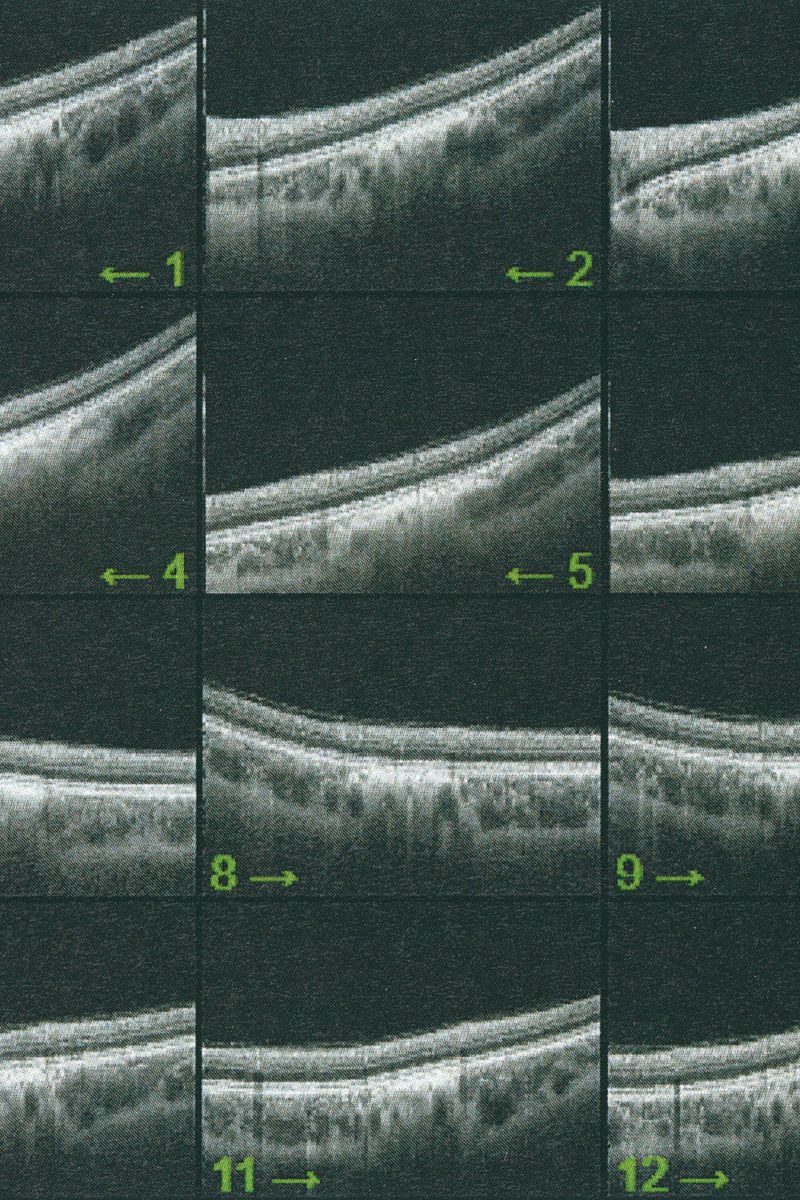

© Eugenio Pancaldi - Image from the Collirio photography project

Le Regard, George Salles. The first book in which is presented the idea of a visuality altered by culture and technology and thus historically situated.